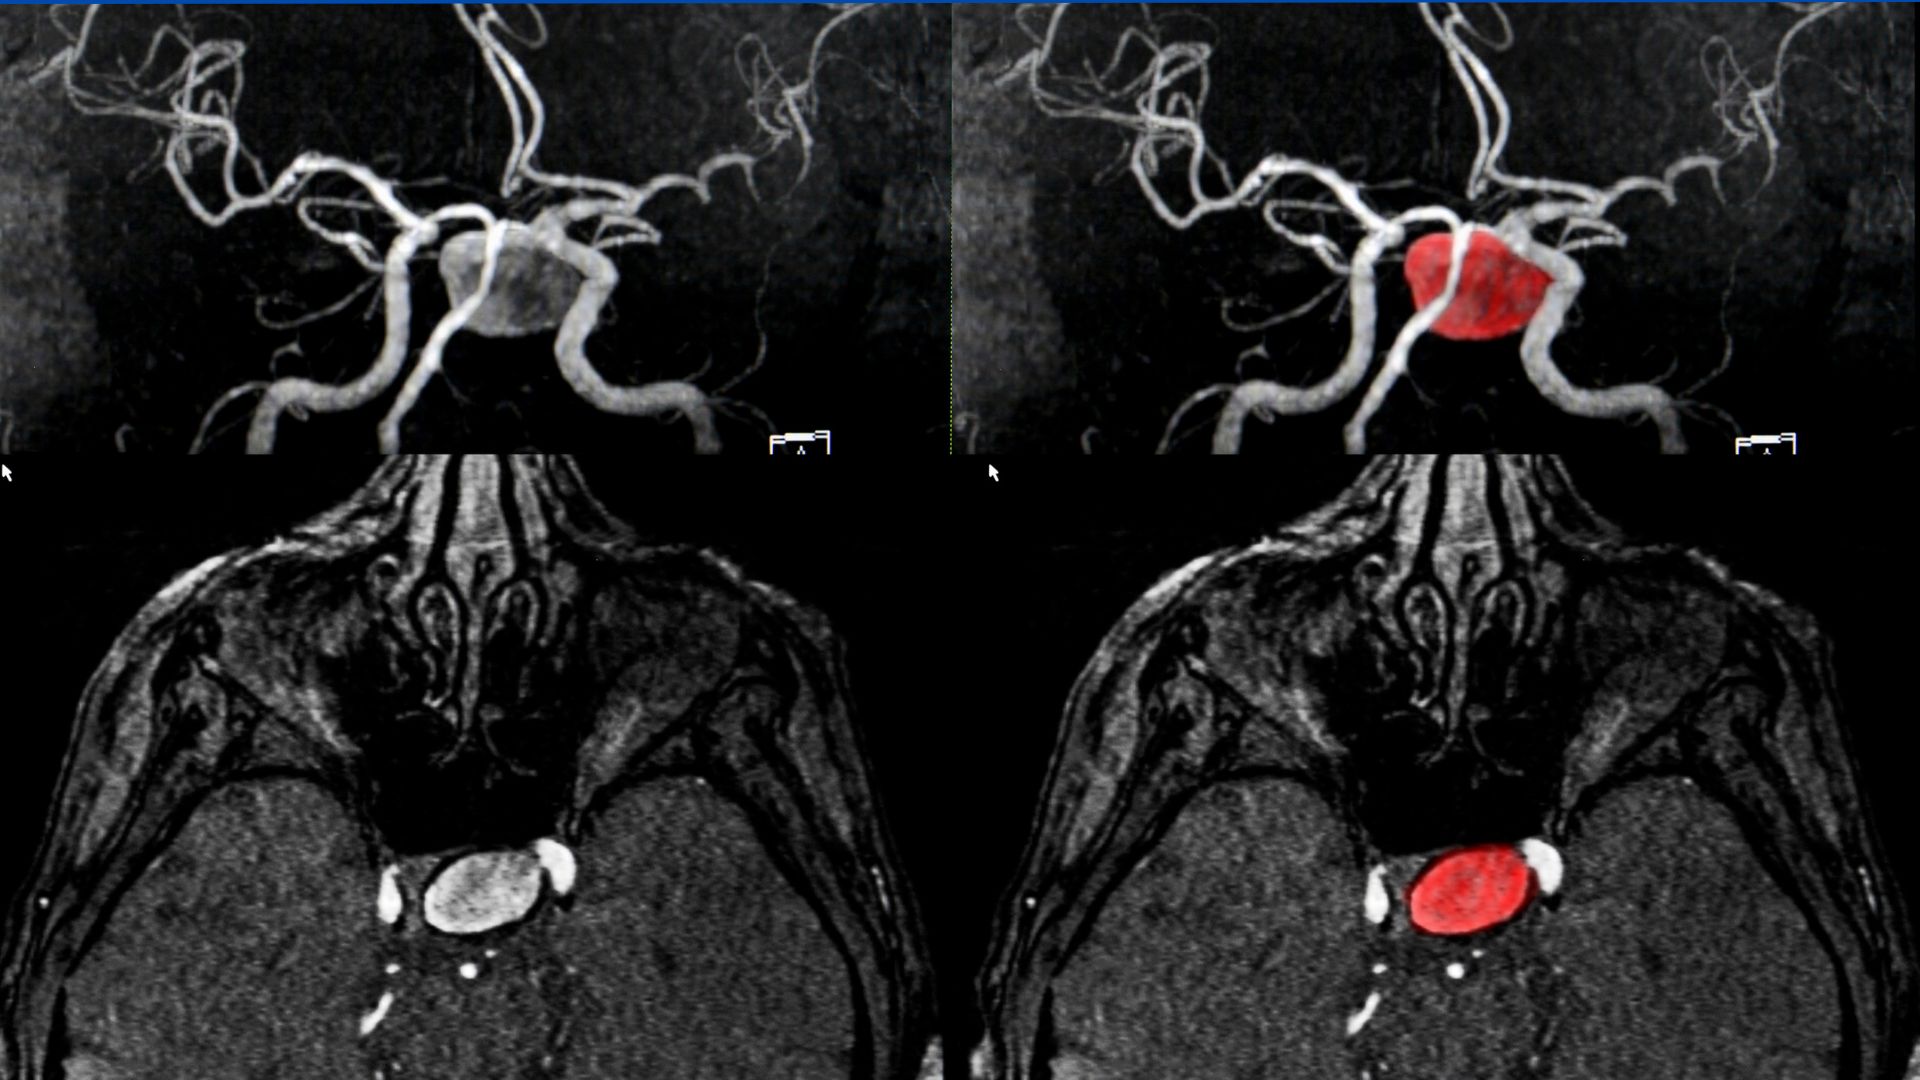

Aneurysm coiling, also known as endovascular coiling, is a minimally invasive procedure used to treat brain aneurysms. During the procedure, a catheter is inserted into an artery in the groin and carefully guided to the brain artery containing the aneurysm. Tiny coils are then placed within the aneurysm to prevent blood flow, reducing the risk of rupture.

How It Works

- A catheter is inserted into an artery in the groin.

- X-rays help guide the catheter into the brain artery.

- The catheter is maneuvered into the aneurysm.

- Tiny platinum coils are placed inside the aneurysm.

- The coils conform to the shape of the aneurysm, promoting clotting and sealing off the aneurysm.